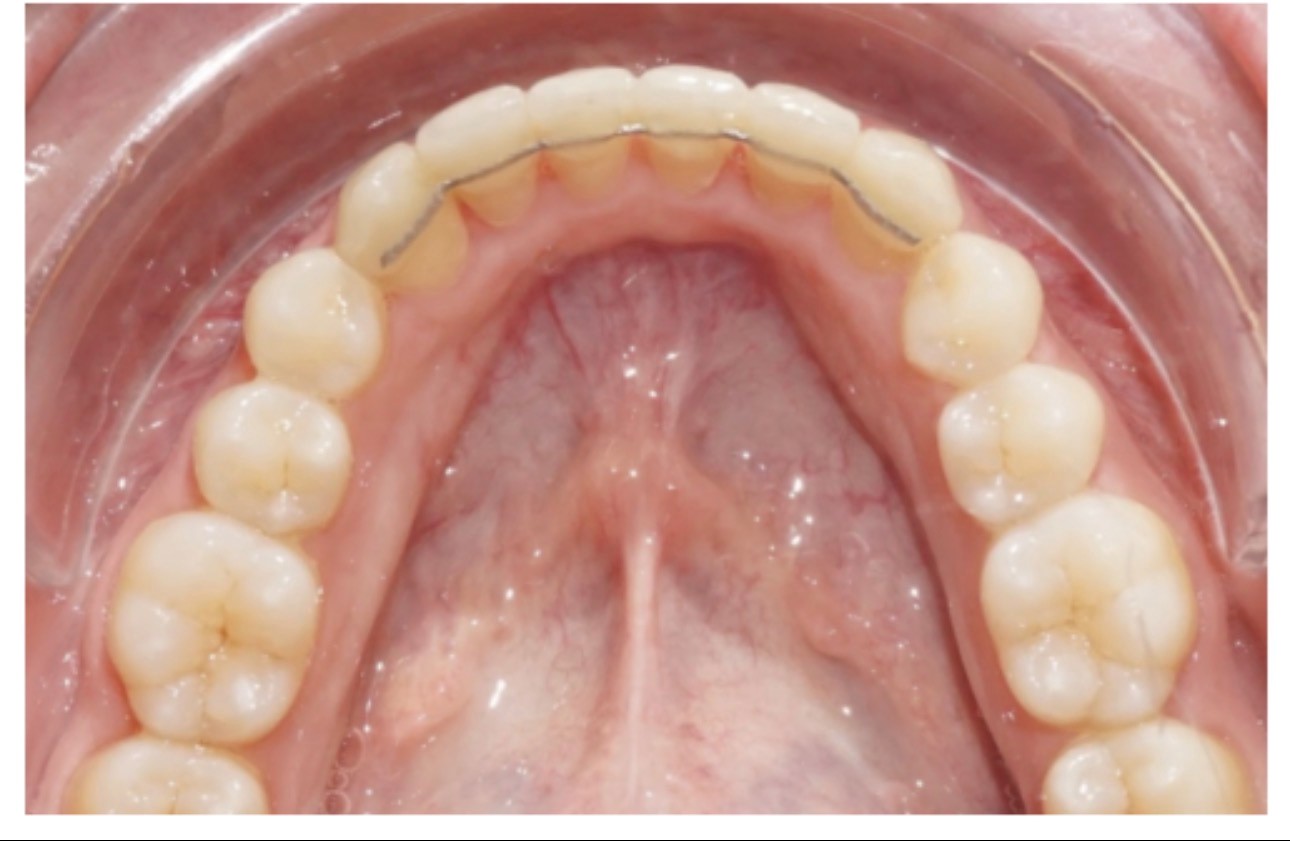

Traitement lingual

Contention